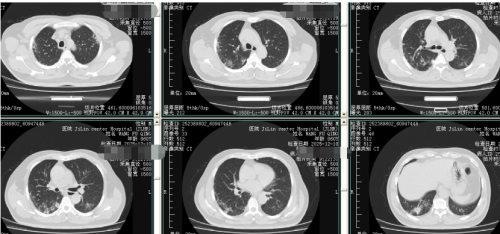

呼吸道病原体基因8项:鼻病毒、副流感病毒,肺炎链球菌。肺ct如下:

12.10我院门诊肺ct:肺内炎症、间质性炎症,治疗后复查。双肺多发结节,双侧胸膜增厚。纵隔增大淋巴结。抗炎后复查。